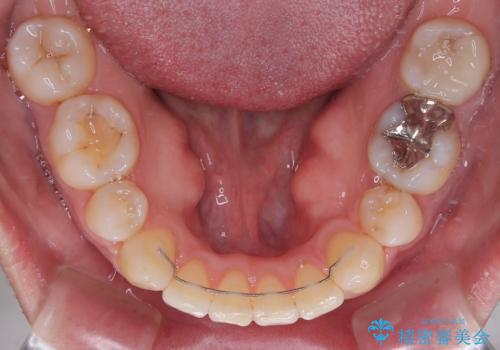

- 口元の突出感と下の前歯のがたつきを主訴として来院された患者様です。

口元の突出感と叢生改善のため上下左右の第一小臼歯4本を抜歯し、ワイヤー装置にて矯正治療を行うこととしました。

なるべく目立たない装置が希望だったため、審美装置で治療を行いました。

左上はアンカースクリューを併用することでスムーズに抜歯スペースを閉じることができました。

口元の突出感もなくなり満足されました。